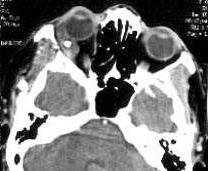

3.其他檢查鱟溶解物實驗(LLT)可檢測血清等標本中革蘭陰性桿菌的內毒素,但不能鑑別為何種病原菌,對診斷革蘭陰性敗血症有一定幫助。病程中如出現心、肝、腎等臟器損害,或休克、DIC等時,應作相應檢查。化膿性關節炎在發病2周后X線檢查才有所發現。